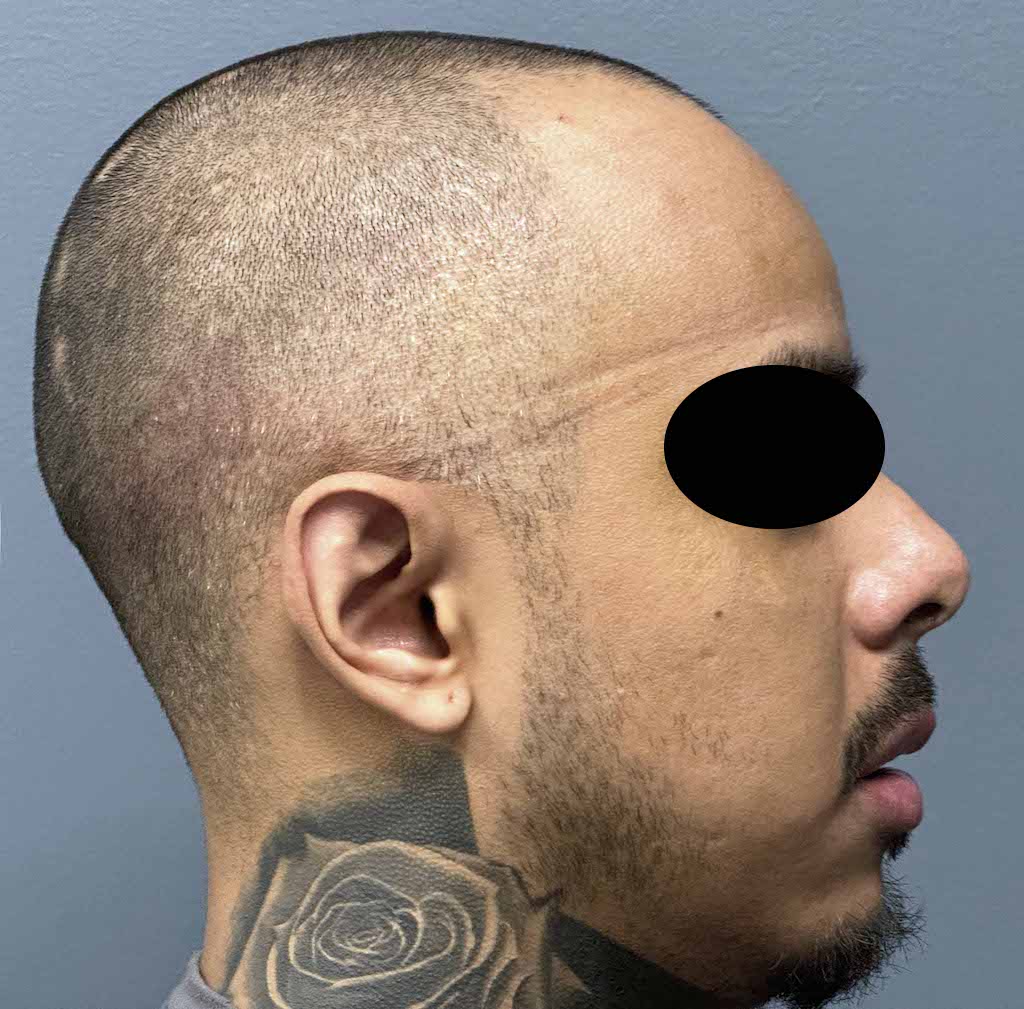

Patient 100

Desire for reshaping of an asymmetric flat back of the head in a shaved head male.

A combined back of the head reshaping procedure was done with a custom skull implant, sagittal ridge reduction and a right temporal muscle reduction.

Desire for reshaping of an asymmetric flat back of the head in a shaved head male.

A combined back of the head reshaping procedure was done with a custom skull implant, sagittal ridge reduction and a right temporal muscle reduction.